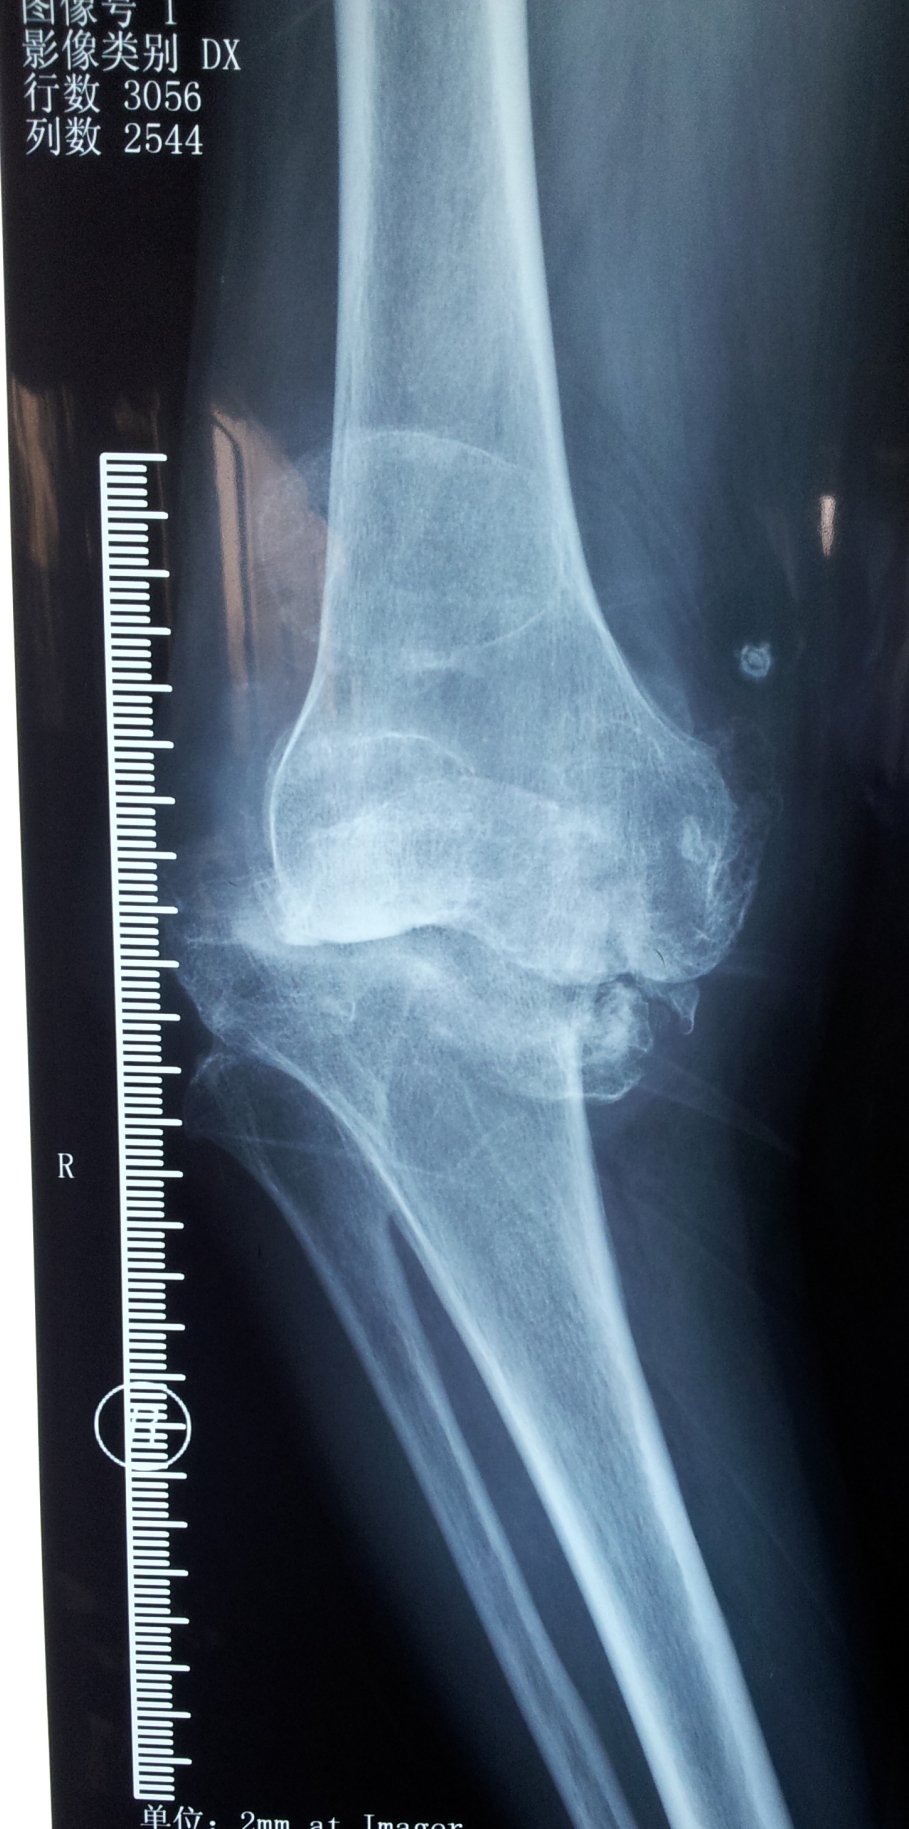

典型病例:患者,女,60岁,右膝骨性关节炎(重度内翻畸形)

术前                           术后

术前 正位                    术后正位